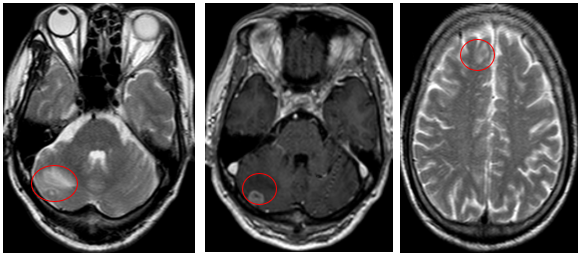

Ca lâm sàng:Hiệu quả điều trị đích bằng Osimertinib ở bệnh nhân UT biểu mô tuyến của phổi giai đoạn IV có đột biến gen EGFR L858R (Exon 21) tại Trung tâm YHHN&UB-Bệnh viện Bạch Mai